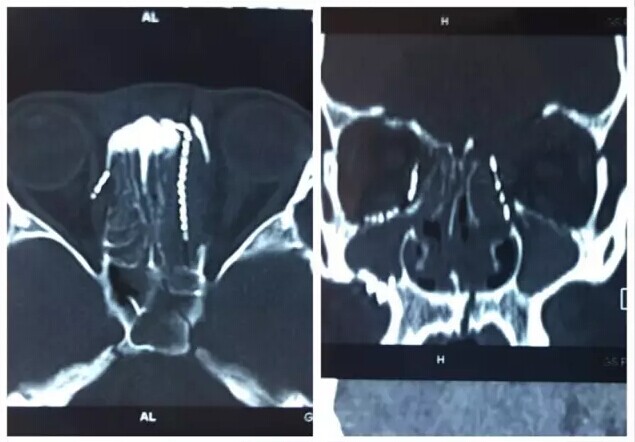

甘肃省二院眼科开展经眼眶视神经减压术使许多外伤失明的患者重见光明------2017-04-28 发布时间:2017-04-28 来源: 作者: